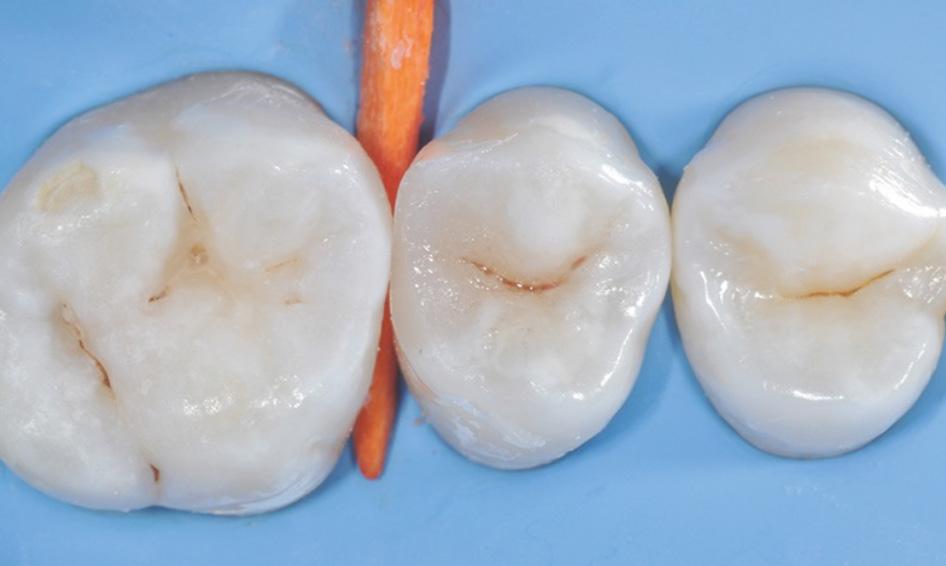

Fig. 9: After removal of the matrix band, the composite was cured for 10 seconds on both the buccal and lingual surface.* Fig. 10: After finishing and pre-polishing, the 3M™ Sof-Lex™ Diamond Polishing System on moist surface was used to create a high gloss polish.

Fig. 11: Final outcome using 3M™ Filtek™ One Bulk Fill Restorative.